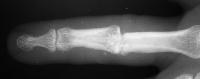

Clinical Example: Avanta proximal interphalangeal joint surface replacement arthroplasty

This young man had been treated for a rotating blade injury of the ring finger proximal interphalangeal joint. He had gross instability, pain and stiffness. These radiographs are before and after proximal interphalangeal joint reconstruction with the Avanta proximal interphalangeal joint surface replacement implant arthroplasty.

Anteroposterior view:

Click for larger image